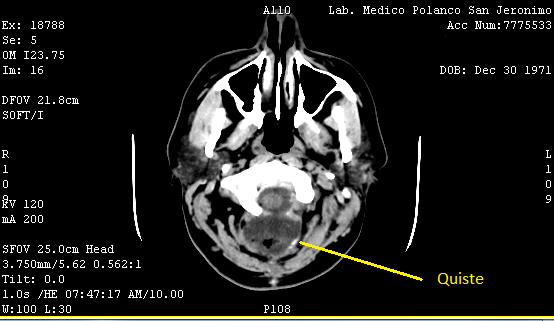

El 13 de diciembre tuve mi primer control fuera del hospital, previo a la cita, me saqué una tomografía y el ultrasonido. El doctor quería ver si el quiste redujo su tamaño, y así fue pero me pidió seguir con la medicina para el cerebro y el vendaje, del acné me dijo que iba a tardar algunos meses, lo mismo que la retención de líquidos, que no me preocupara por el peso ya que en unos meses, mi cuerpo eliminaría esos kilos de manera natural. Lo que no le gusto fue mi semblante, estaba demasiado pálida y amarilla así que me mando estudios.